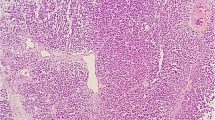

LEF-1 expression

Using the clone EP310 antibody, LEF-1 was detected in 8 of 30 (26.7%) MBs (Fig. 2). Among them, 5 (16.7%) cases were partial staining, while 3 (10%) cases showed diffuse strong staining. In these 5 LEF-1 partially expressed MBs, 3 cases were desmoplastic/nodular MBs histologically, one was classic, and one was were anaplastic/large cell MB. All the 5 LEF-1 partially expressed MBs were grouped into SHH-activated subtype. For 3 MBs cases with LEF-1 diffuse and strong expression, all showed classic histological feature, and genetically were WNT-activated MBs (Table 2). WNT-activated MBs correlate significantly with nuclear LEF-1 staining. No correlation was found between LEF-1 expression and histological subgroups.

LEF-1 and β-catenin expression pattern in different histological and genetical MB. LEF-1 and β-catenin expression in WNT-activated MB, H&E staining showed classic histological features (a), diffuse nuclear LEF-1 expression (b), and focal nuclear β-catenin expression (c). A case of SHH-activated MB showed desmoplastic/nodular features (d, H&E staining), focal LEF-1 (e) and no nuclear β-catenin expression (f). A case of Group 4 MB showed Anaplastic/large cell features (g, H&E staining), no LEF-1 expression (h) and no nuclear β-catenin expression (i)

β-catenin expression

Detecting the protein expression using the clone UMAB15 antibody, All the MBs cases showed tumor cell membrane/cytoplasm expression of β-catenin. Only four MBs showed focal scattered nuclear staining of β-catenin with percentage of stained tumor cell less than 1% (Fig. 2). Three out of the four β-catenin nuclear expression cases were classified as classic WNT-activated MBs. The other one was molecular SHH-activated and histological anaplastic/large cell MB (Table 2). WNT-activated MBs correlate significantly with nuclear β-catenin staining. No correlation was found between nuclear β-catenin expression and histological subtypes. Our result also confirmed LEF-1 protein expression level was correlated with nuclear expression of β-catenin (p < 0.001).

Lymphoid enhancer-factor 1 (LEF-1), a transcription factor that binds DNA in a sequence-specific manner with β-catenin, but has not been fully studied in MBs. Activation of WNT / β-catenin signaling pathway results in reduced degradation of β-catenin, which leads to increased cytoplasmic β-catenin enter the nucleus, and combined with the nuclear transcription factor TCF/LEF-1 to form a transcription complex and regulate the transcription of downstream target genes, such as C-Myc and Cyclin D1 [31, 32]. In vitro, the two proteins bind in a highly cooperative manner [33]. LEF-1 acts like a nuclear anchor, β-catenin can direct interaction with that, providing a molecular mechanism for the transmission of signals to nuclear, driving tumor formation. In addition, β-catenin strongly enhances transcription by LEF-1 in a chromatin-dependent manner on a minimal enhancer composed of reiterated TCF/LEF-1 binding sites in vitro [34]. Considering the close functional relationship between LEF-1 and β-catenin, we speculate that LEF-1 may be a useful marker predicting WNT-activated MBs. In our study, the expression of LEF-1 was detected by immunohistochemistry and compared with β-catenin. Our results clearly showed that LEF-1 expression was significantly related with WNT-activated MBs. We did not find any LEF-1 expression in non-Wnt/non-SHH MBs. For these 3 LEF-1 diffuse strongly expressed MBs, all showed classic histological feature, and geneticlly defined as WNT-activated MBs, while β-catenin expression was difficult to read, and less than 1% tumor cells showed nuclear β-catenin staining for the 4 positive cases. Thus, immunohistochemical staining of LEF-1 can be used as a supplement for β-catenin to diagnosis WNT-activated Medulloblastomas, when β-catenin is difficult to recognize for its cytoplasm/membrane staining background.